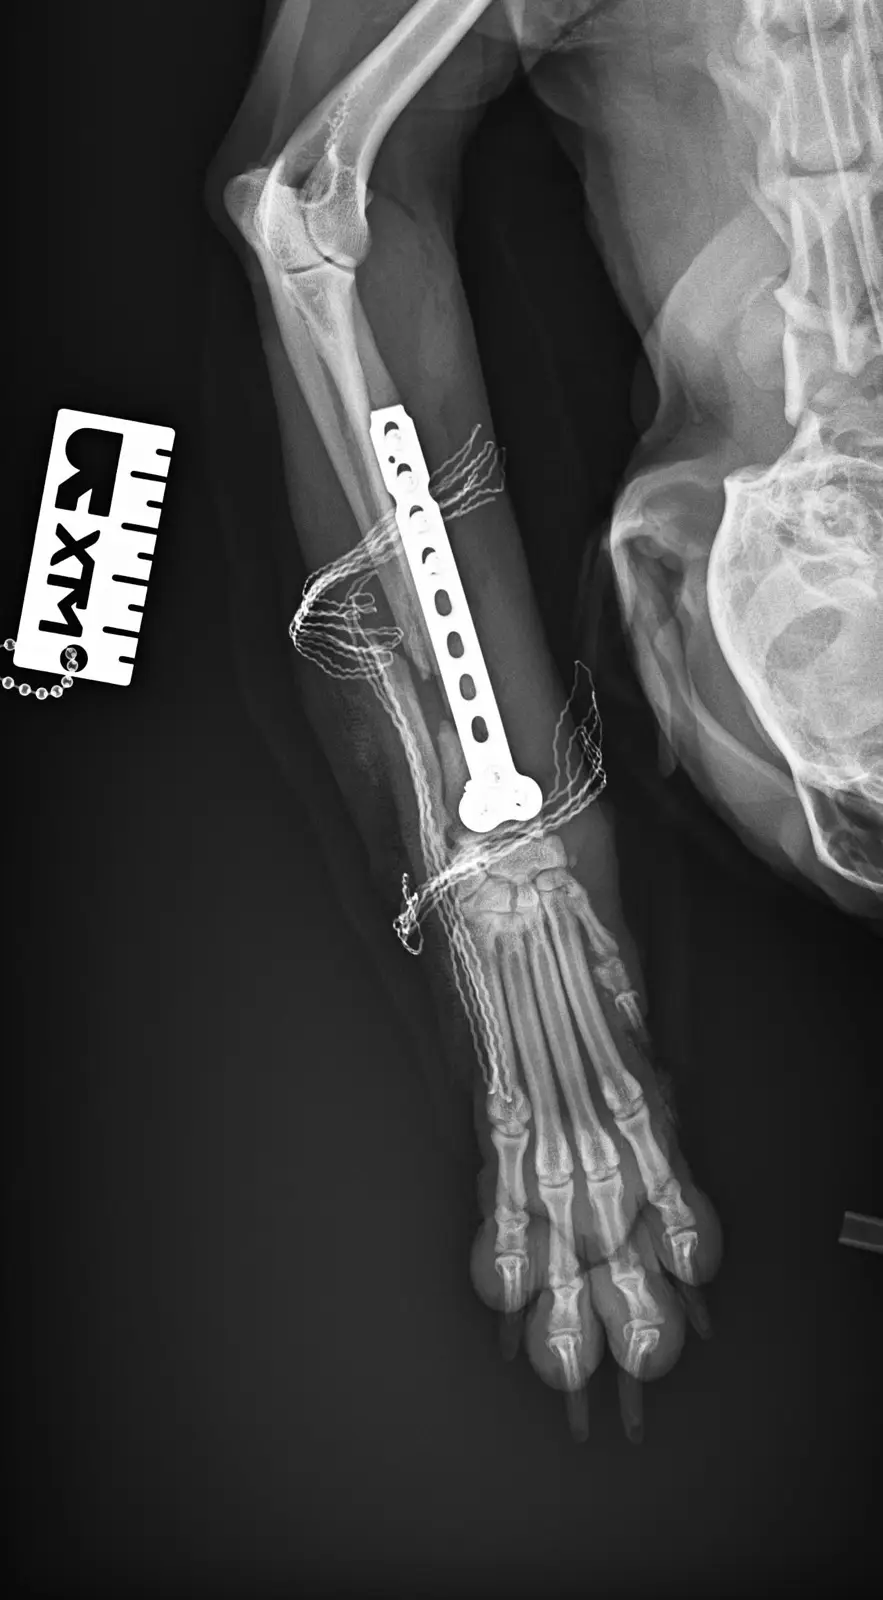

Моля ,който може да помогне !На 29.10 беше първата му операция  за открита фрактура на предна дясна лапа оператор  е  д-р Йордан Стоянов ортопед и на 31.10  беше втората много тежка операция на множество фрактури на таза и за луксациите на двете тазобедрени стави

Please who can help !On 29.10 was his first surgery for open fracture of front right paw operator is Dr. Jordan Stoyanov orthopedist and on 31.10 was the second very severe surgery for multiple fractures of the pelvis and for the luxations of both hip joints